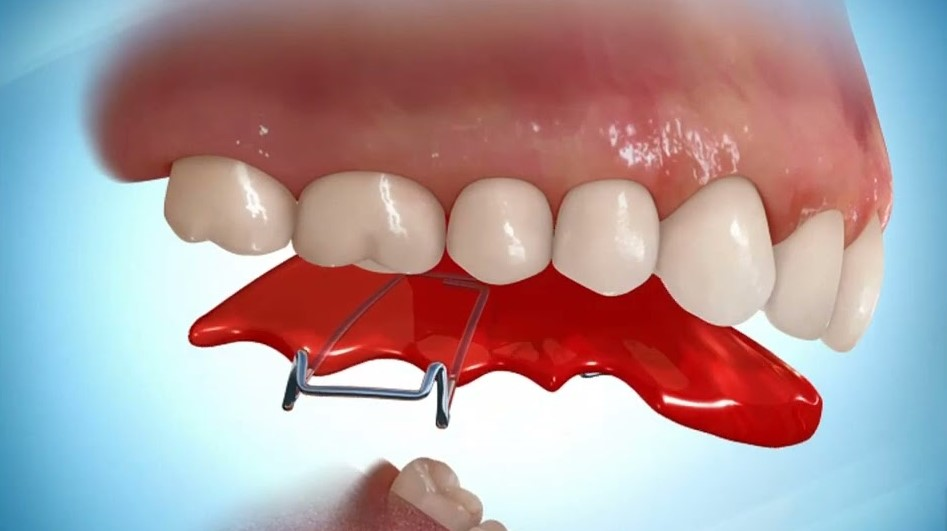

3) Upper removable appliance (URA)

URAs are acrylic-based appliances with metal wires attached. They are used for the upper arch of teeth and are used to improve your teeth’s aesthetic and function. When a flat anterior bite plane is added to the URA, a deep bite can be corrected by inducing your back molars to erupt further out, thus reducing the deep bite.